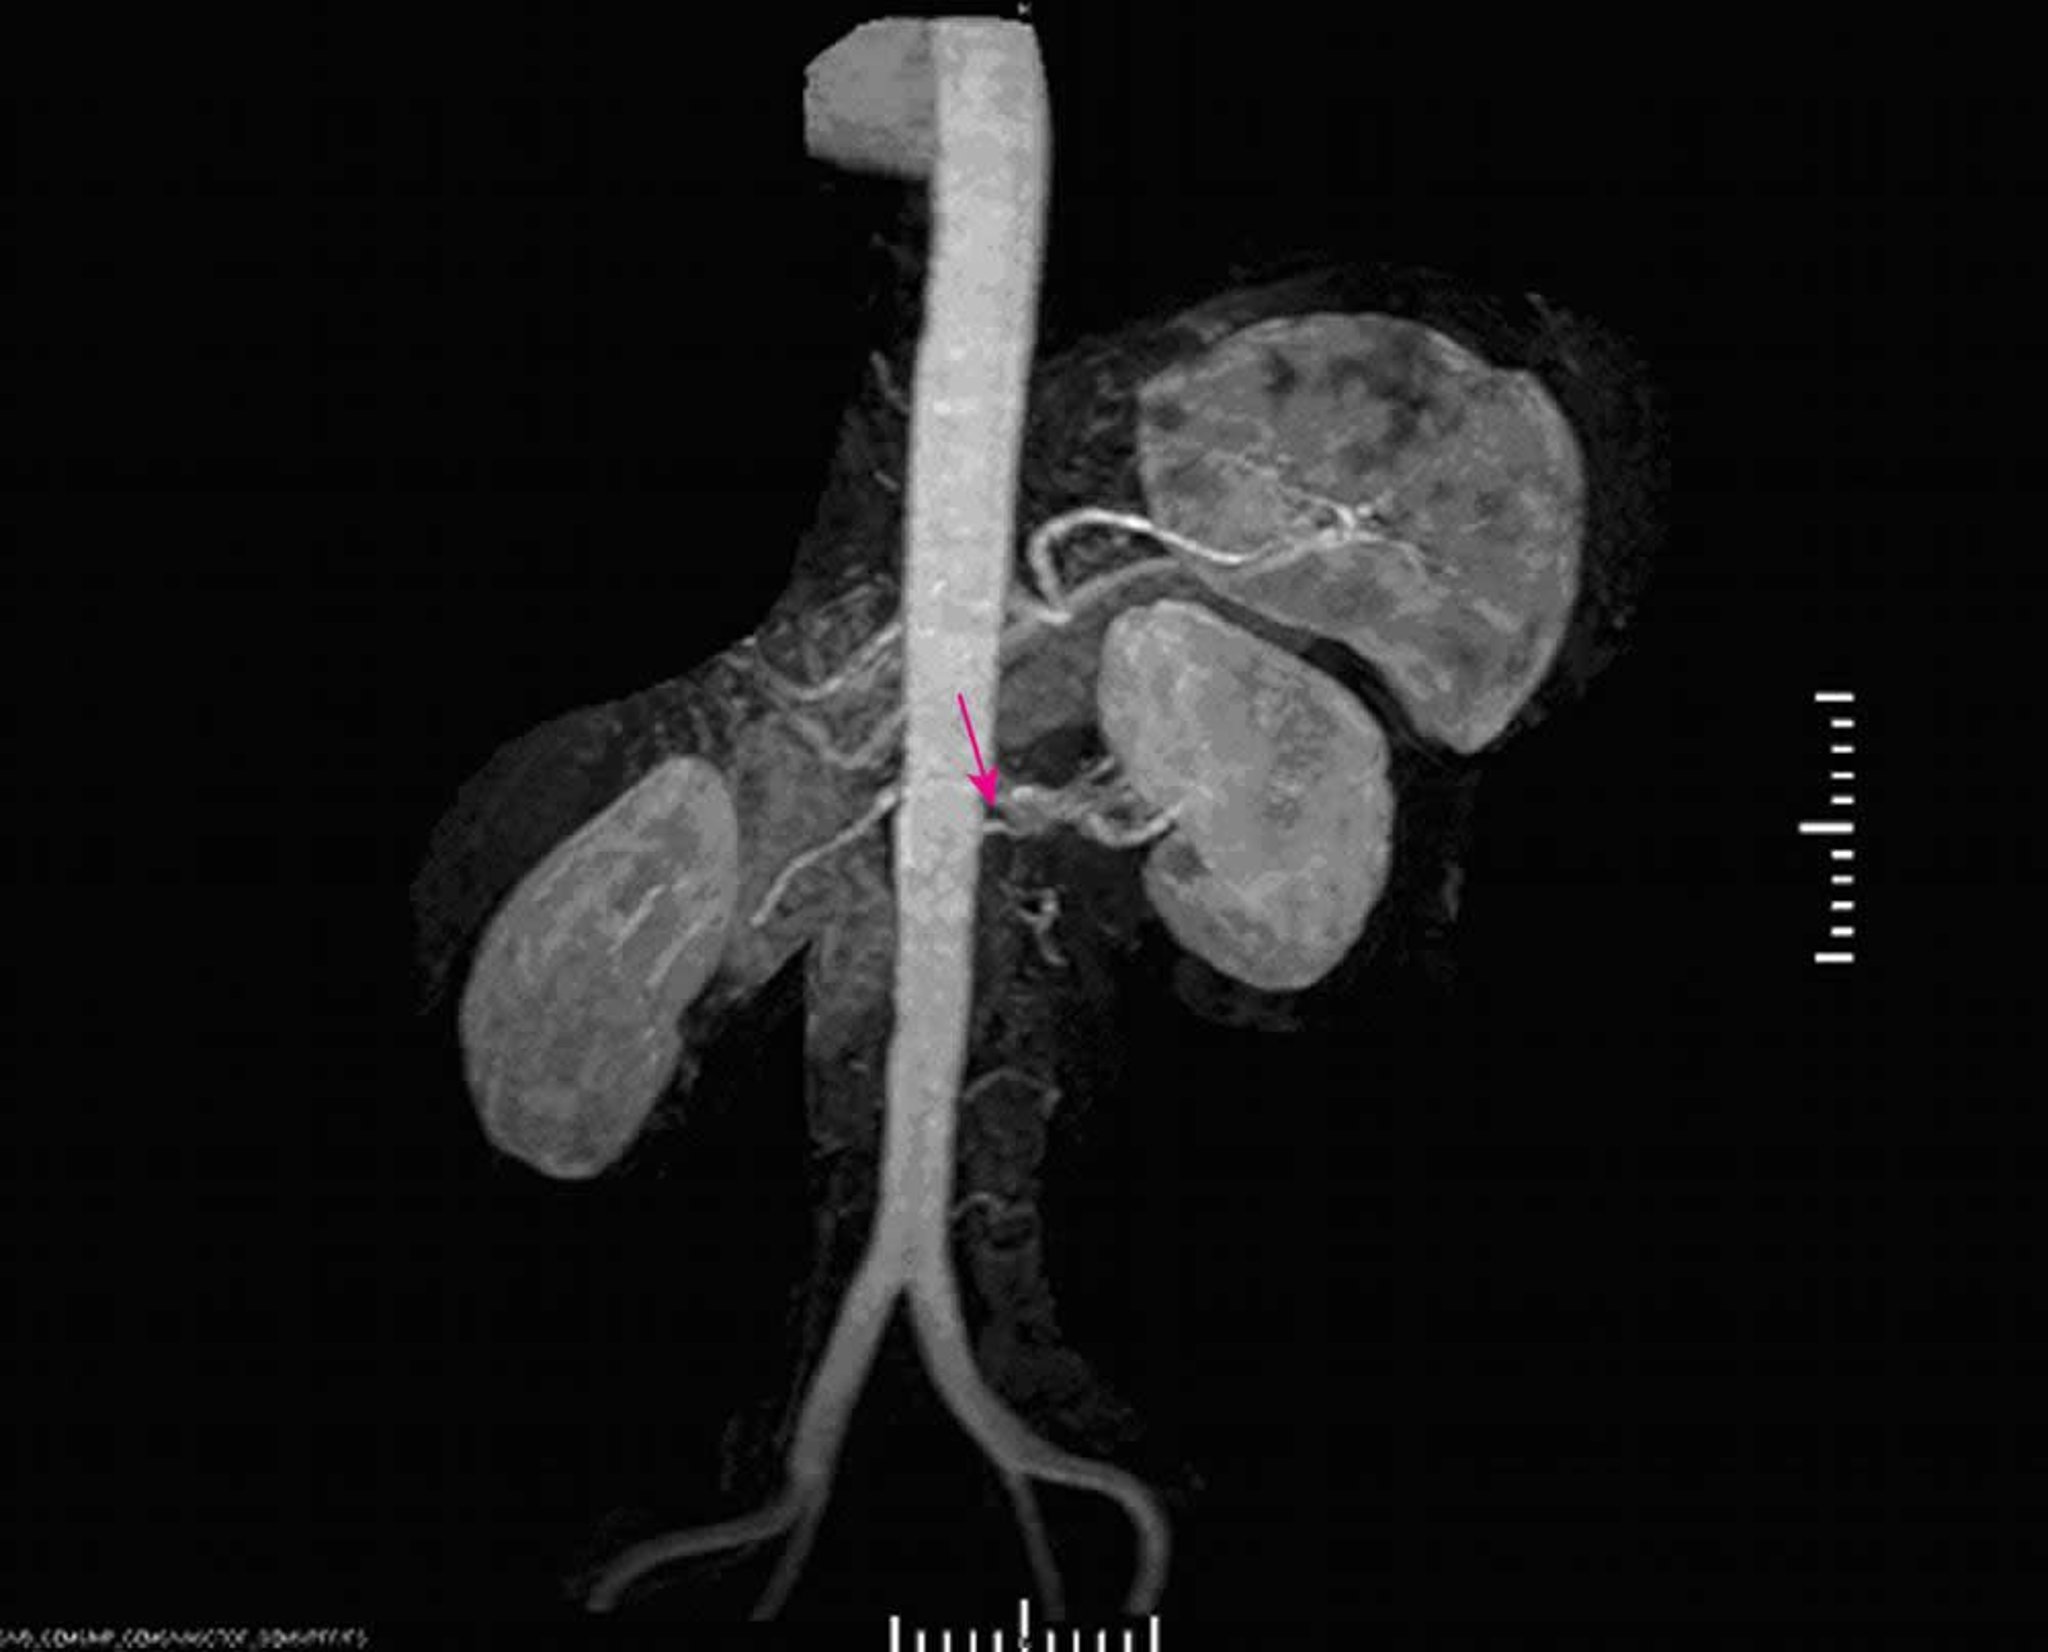

Ipertensione nefrovascolare (angiografia a RM)

L'angiografia con RM dimostra una grave stenosi all'origine dell'arteria renale principale sinistra.

Image provided by Jan N. Basile, MD.